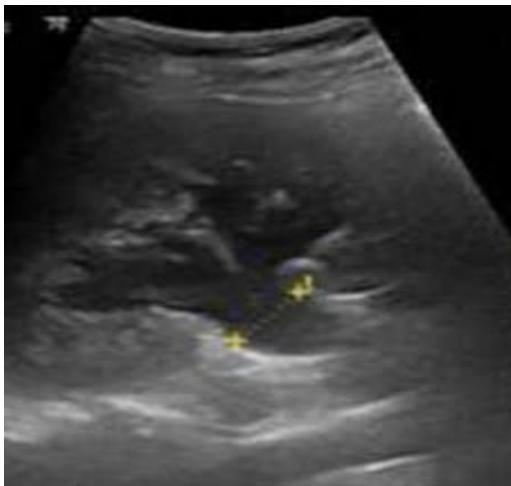

Pyelonephritis was again documented, for which the patient was hospitalized to start intravenous in-hospital antibiotic management (ampicillin/sulbactam, 3 g IV every 6 hours) and a urine culture was requested, renal and urinary tract ultrasound was performed, reporting a finding of bilateral hydronephrosis. grade II without findings of renal lithiasis or other alterations (figure 1). Patient who remained 4 days of hospitalization under antibiotic treatment mentioned above with stable evolution, however, on the 5th day of hospitalization he presented abrupt torpid evolution of his clinical picture with blood pressure figures with a tendency to hypotension, tachypnea, tachycardia (blood pressure 80/50mmHg, respiratory rate 28rpm, heart rate 112lpm, wakes up to verbal stimulation) (omSOFA: 2pts), then considering a diagnosis of sepsis of urinary origin, for which it was indicated to stagger antibiotic treatment to piperacillin/tazobactam at a dose of 4.5gr IV every 8 hours, a bolus of 2000cc (30cc/kg) was administered and basal fluids were continued at 100cc/hr; extension laboratories for sepsis were requested (Table 3) and transfer to the intensive care unit for comprehensive management was indicated.

Figure 1: Renal and urinary tract ultrasound, coronal section. Grade II right hydronephrosis. Source: authors.